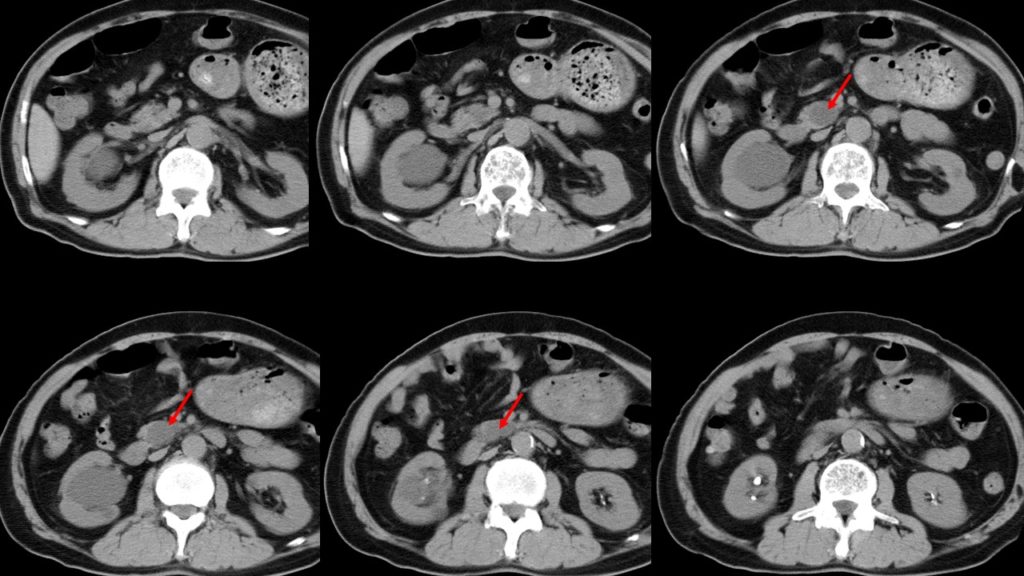

嚢胞(のうほう)とは液体の入った風船のような袋のことであり、膵臓の中もしくはその周囲にできた嚢胞を膵嚢胞と呼びます。 多くの場合、無症状であり、画像診断の進歩により健診などで偶然発見されるケースが増えてきました。 大きさは数㎜程度の小さなものから10cmを超えるものまでさまざまであり、1個だけの場合もあれば複数個認める場合もあります。 がん化の可能性があるIPMN. 膵嚢胞は、腫瘍性嚢胞と非腫瘍性嚢胞に大きく分けられます。 さらに前者は膵管内乳頭粘液性腫瘍(IPMN)、粘液性嚢胞腫瘍(MCN)、漿液性嚢胞腫瘍(SCN)など、後者は膵臓仮性嚢胞、リンパ上皮嚢胞などに分類されます。 膵管内乳頭粘液性腫瘍(IPMN). 膵嚢胞性腫瘍とは?. 膵嚢胞性疾患は、膵臓にできる嚢胞(ふくろ状の)の形態をとる腫瘍の総称で、治療の必要のない良性の腫瘍や炎症性疾患もあれば、悪性リスクのある腫瘍もあり、いくつかの異なった疾患をまとめた疾患概念です。. 近年、膵嚢胞性.

嚢胞ってどんなもの?. 嚢胞とは体内にできる袋状の病変(病気によって起こる体の変化)で、その中には液状の内容物が入っています 。. ほとんどの嚢胞はその内側が上皮によって覆われています。. ちなみに、 内容物が固体の場合は嚢腫(のうしゅ) と.. 膵のう胞【すいのうほう】とは、膵臓の中や周りに いろんな大きさの「袋」 ができる病気です。 ほとんど 症状がなく 、嚢胞の 種類によって治療が異なる ので、詳しく調べる必要があります。 膵のう胞は、どんな病気? 膵のう胞【すいのうほう】とは、 膵臓の中や周り に いろんな大きさの「袋」 ができる病気です。 袋の中には、液体やねばねばとした液などが溜まっています。 CTやお腹のエコー検査などをして、 偶然発見 されることの多い病気です。 膵のう胞は、すぐに手術が必要なものから定期的に診察が必要なものまで様々で、種類が何であるかを詳しく調べる必要があります。 全人口の約2~3%の人が、膵のう胞を合併しているという報告もあり、決してまれな病気ではありません。